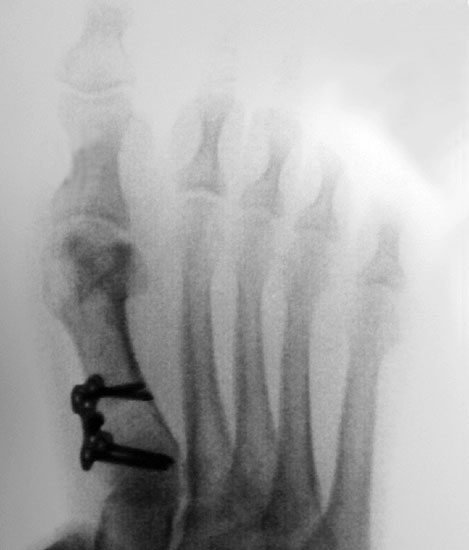

Beim Follow up nach 6 Monaten zeigte sich eine Korrektur des ersten Intermetatarsalwinkels (IMW) um durchschnittlich 9° (Range 4-15°) auf Normwerte (6,8° SD 1,3) (Abb. 21).

Gutes postoperatives Ergebnis mit physiologischem Intermetatarsale I-II Winkel nach open wedge Osteotomie.

Abbildung 21

In zwei Fällen kam es intraoperativ zu einem Bruch der lateralen Kortikalis. In einem Fall konnte durch die winkelstabile Platte eine ausreichende Stabilität erzielt werden, in dem anderen Fall wurde zusätzlich ein perkutaner Kirschnerdraht eingebracht, der nach 6 Wochen entfernt wurde. Eine stabile knöcherne Konsolidierung der Osteotomie ohne Korrekturverlust konnte in beiden Fällen erreicht werden. Die Analyse der Röntgenaufnahmen ergab eine Verlängerung des Os metatarsale I von durchschnittlich 1,8 mm (Range 1-4 mm).